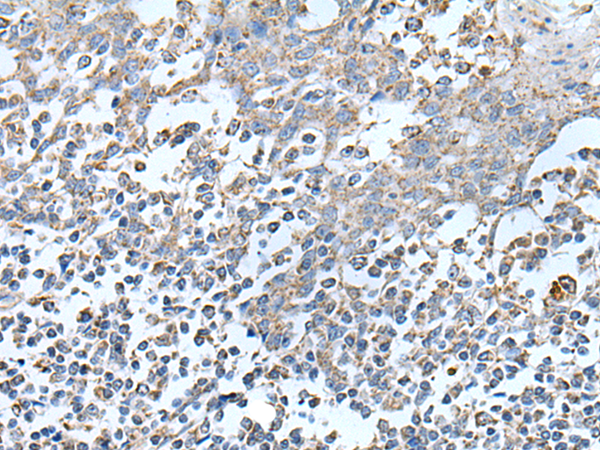

IHC positive control: |

Human cervical cancer and human tonsil |

IHC Recommend dilution: |

25-100 |